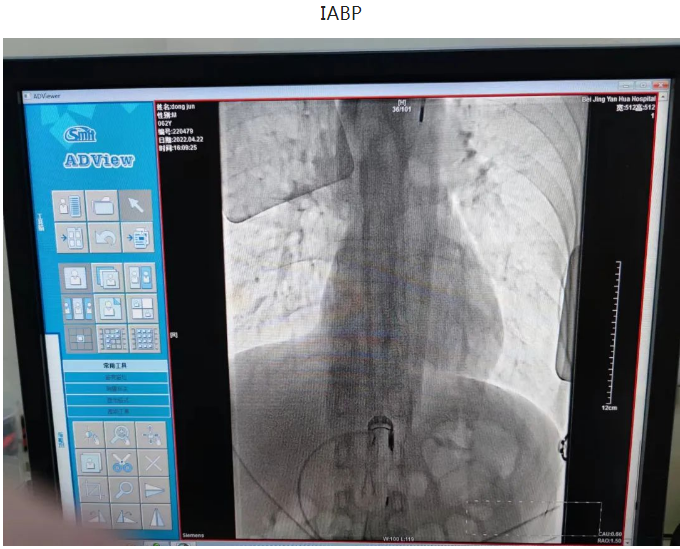

一日凌晨,68岁的石大爷睡眠中突发心前区压榨样疼痛,伴一过性意识丧失,跌倒在地,二便失禁,并胸痛持续不缓解,呼叫120送至我院急诊,心电图提示急性下壁心肌梗死,III度房室传导阻滞,血压74/38mmHg,急诊立即排查新冠肺炎的同时联系我科,秦鹏主治医师立即开通心肌梗死绿色通道,做好防护隔离的同时给予患者静脉溶栓治疗,治疗后患者症状缓解,心电图恢复窦律,抢救成功,后完善冠脉造影提示患者冠脉三支血管病变,右冠状动脉细小,前降支闭塞,回旋支狭窄并可见血栓,李钢主任与患者家属充分交待病情,患者三支血管只剩一支并且是本次心梗的血管,病情危重,需要处理回旋支并尝试开通前降支血管,手术难度及风险较高,患者家属表示理解并要求积极抢救,李刚主任及王志勇、刘丹亮副主任医师给予患者置入IABP(主动脉内球囊反搏)作为保护,反复尝试后给予患者回旋支及前降支闭塞血管进行了治疗,植入冠脉支架,患者转危为安,术后持续IABP辅助,心功能逐渐恢复,抢救成功。

第二日晨,3年前冠脉置入一枚支架的62岁的董大爷干农活时突发咽部紧缩感,伴胸闷不适,持续不缓解,呼叫120送至我院急诊,血压75/56mmHg,急诊考虑急性下壁心肌梗死,心源性休克,急诊立即排查新冠肺炎的同时联系我科,做好术前准备后急送至导管室,冠脉造影可见原支架位于左主干至前降支近段,回旋支消失不见,李钢主任反复尝试后找到回旋支开口,并给予成功重新开通血管,患者血流恢复,症状缓解,但血压持续偏低,考虑患者心源性休克,给予患者置入IABP(主动脉内球囊反搏)作为辅助,患者心功能逐渐恢复,治愈出院。